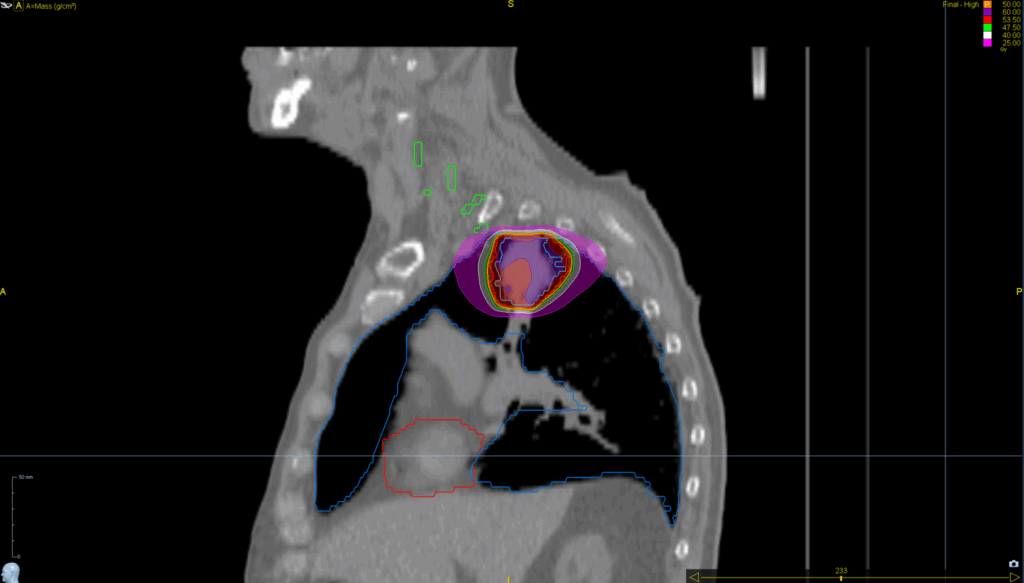

Treatment Plan Images

Fractionation / Protocol Used

50 Gy in 5 fractions

PTV(s) Volume

5 cm, 55 cc

Mode

- Tomohelical™

- Synchrony® Lung™

- SBRT

- TomoEDGE™ 2.5 cm

Planning Time Optimized with VOLO™ Ultra

40 min